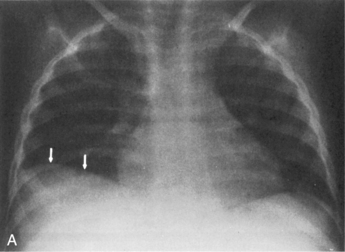

If the clear silhouette between the air density of the lungs and the tissue density of the diaphragm is obscured, it is usually caused by basilar atelectasis or accumulation of free pleural fluid along the diaphragm (Fig. 10-5). The accumulation of subpulmonic fluid can create an appearance similar to that produced by an elevated diaphragm if an AP film is taken with the patient upright. The free fluid will be readily apparent, however, when a lateral decubitus film is taken.

image image

Fig. 10-5 Pleural effusion. These films were obtained when this 3-year-old child developed tachypnea and increased respiratory effort several days after repair of a double-outlet right ventricle. The nurse noted a significant decrease in breath sounds over the right lung fields, particularly the right middle and lower lobes. The right lung fields were dull to percussion. The radiograph was ordered to differentiate between atelectasis and pleural effusion. A, The upright anteroposterior film. Despite an apparently good inspiratory film, the right lung field is smaller than the left. This finding could indicate elevation of the diaphragm as a result of atelectasis. It also could represent free pleural fluid accumulation along the diaphragm. The hilar pulmonary vascular markings are somewhat hazy; this is consistent with either atelectasis or compression of the right lung by subpulmonic fluid. The right costophrenic angle is blunted, so the diagnosis of pleural effusion was favored and a decubitus film was ordered to confirm the diagnosis. B, The decubitus film. The film was taken with the child lying on his right side so that the free right pleural fluid accumulated along that side. The fluid level is easily discerned (arrows).

(Courtesy Andrew K. Poznanski, Children’s Memorial Hospital, Chicago, IL.)